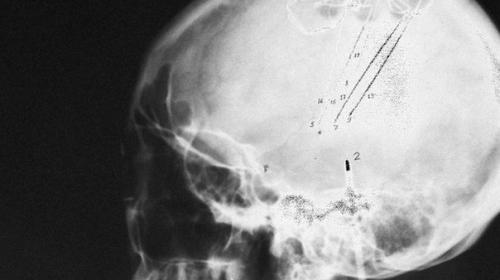

Прибор, представляющий небольшую сеть электродов, имплантируемых в мозг пациента, был разработан в университете южной Калифорнии совместно с медицинским центром Wake Forest, пишет Financial Times. Разработка прибора заняла около 10 лет.

По заявлению разработчиков, основой стал специальный математический алгоритм, способный имитировать электронные сигналы мозга, с помощью которых образуются воспоминания. Считывать воспоминания имплант пока не может, однако он позволит обойти повреждённые участки мозга и сумеет помочь в формировании целого сигнала воспоминаний.

В рамках программ RAM и Remind специалисты пентагона изучают возможности создания своеобразной "Карты" мозга и внедрения туда беспроводного устройства, которое кроме восстановления памяти позволит пользователю подключаться к различным электронным устройствам или другим пользователям.